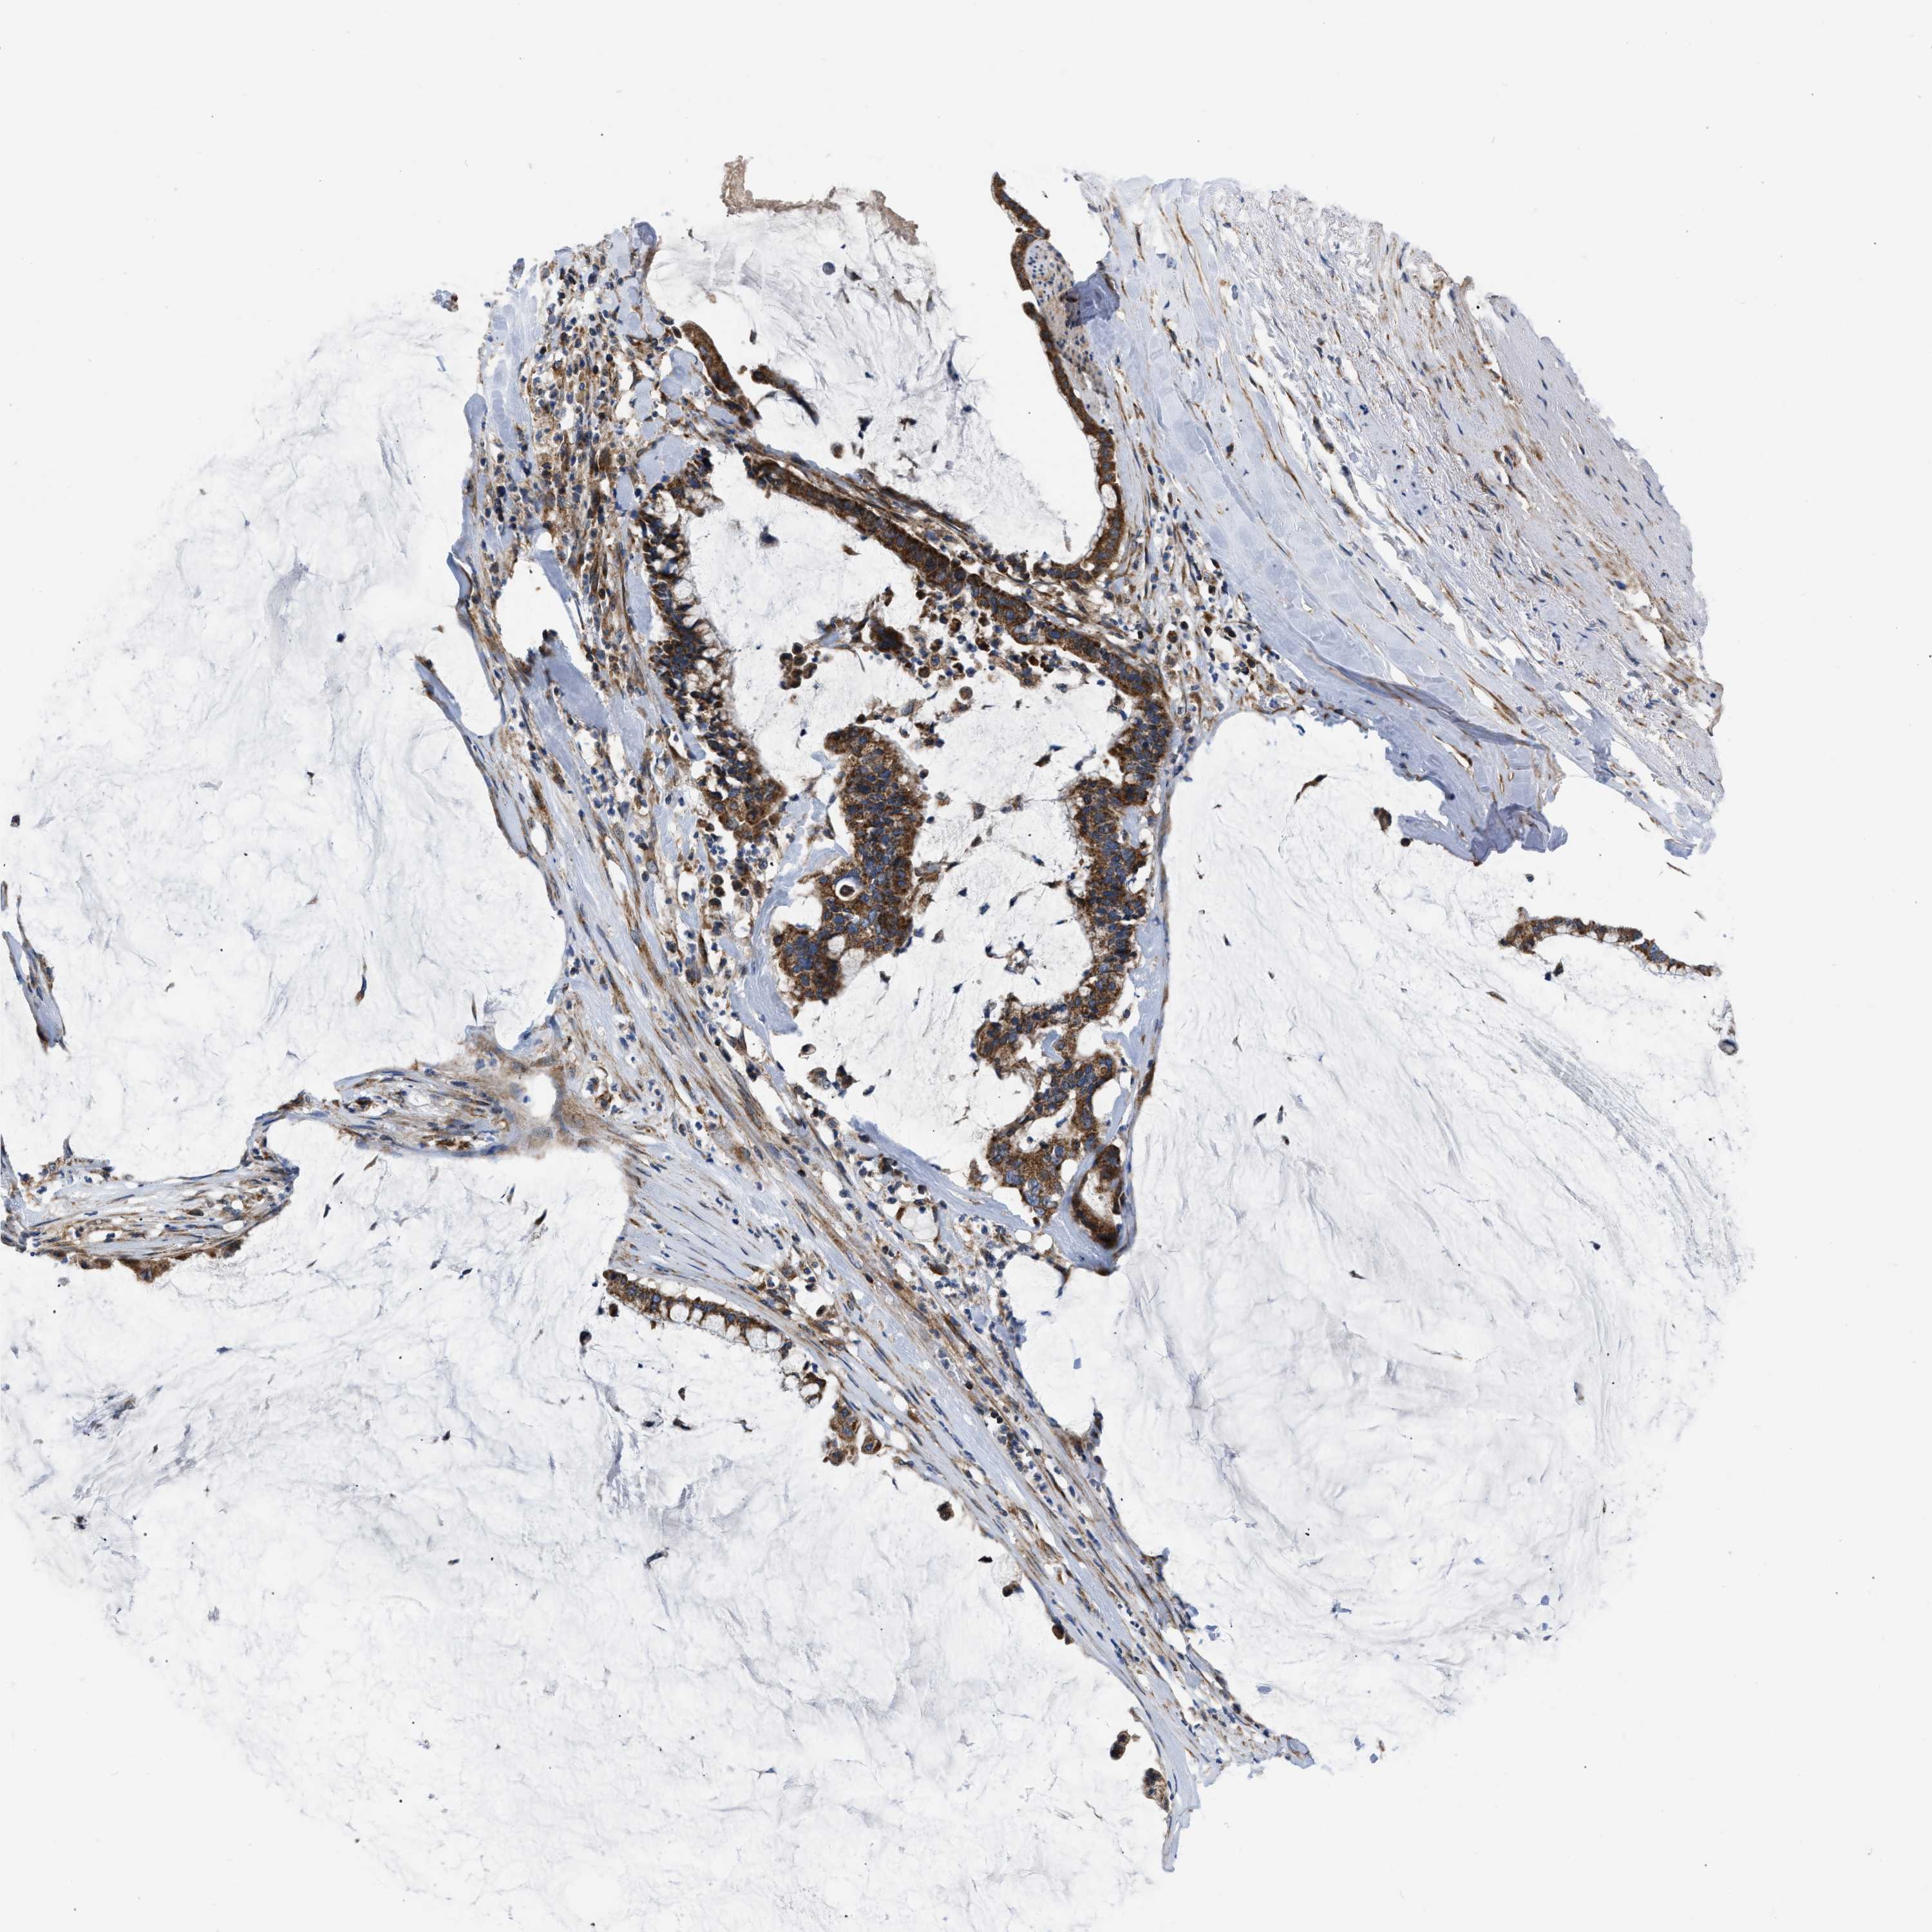

PANCREATIC CANCER - Protein expressioni

A mouse-over function shows sample information and annotation data. Click on an image to view it in a full screen mode. Samples can be filtered based on level of antibody staining by selecting one or several of the following categories: high, medium, low and not detected. The assay and annotation is described here.

Note that samples used for immunohistochemistry by the Human Protein Atlas do not correspond to samples in the TCGA dataset.

Antibody stainingi

Antibody staining in the annotated cell types in the current human tissue is reported as not detected, low, medium, or high, based on conventional immunohistochemistry profiling in selected tissues. This score is based on the combination of the staining intensity and fraction of stained cells.

Each image is clickable and will lead to virtual microscopy that enables deeper exploration of all samples and also displays staining intensity scores, fraction scores and subcellular localization as well as patient and tissue information for each sample.

Antibody HPA003279

Antibody HPA003360

Antibody CAB019303

Staining

High

Medium

Low

Not detected

Intensity

Strong

Moderate

Weak

Negative

Quantity

>75%

75%-25%

<25%

None

Location

Nuclear

Cytoplasmic/membranous

Cytoplasmic/membranous,nuclear

Adenocarcinoma, NOS

Adenocarcinoma, metastatic, NOS